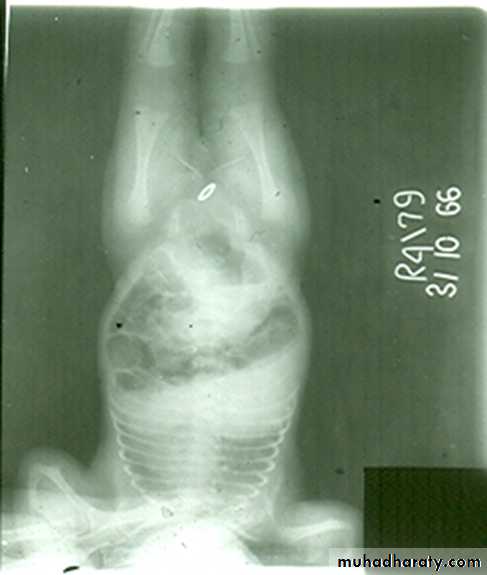

congenital megacolon (Hirschprung disease )

• There is one or more segment of colon devoided from innervation resulting in constriction with proximal dilatation of rest of colon due to weak innervation .• The agangloinic segment usually short , at or near the recto- sigmoid junction .

congenital mega colon

• Rarely the whole colon can be affected result in micro-colon .• 5. Clinically the patient suffering from constipation and abdominal distention since birth .

• 6. The value of Ba Enema is to spot the narrow segment especially prior to surgery .

• 7. Instant Ba Enema is usually done and the Barium used is usually hypertonic .

• Views of particular importance include:

• early filling views that include rectum and sigmoid colon allowing for rectosigmoid ratio to be determined.

• transition zone